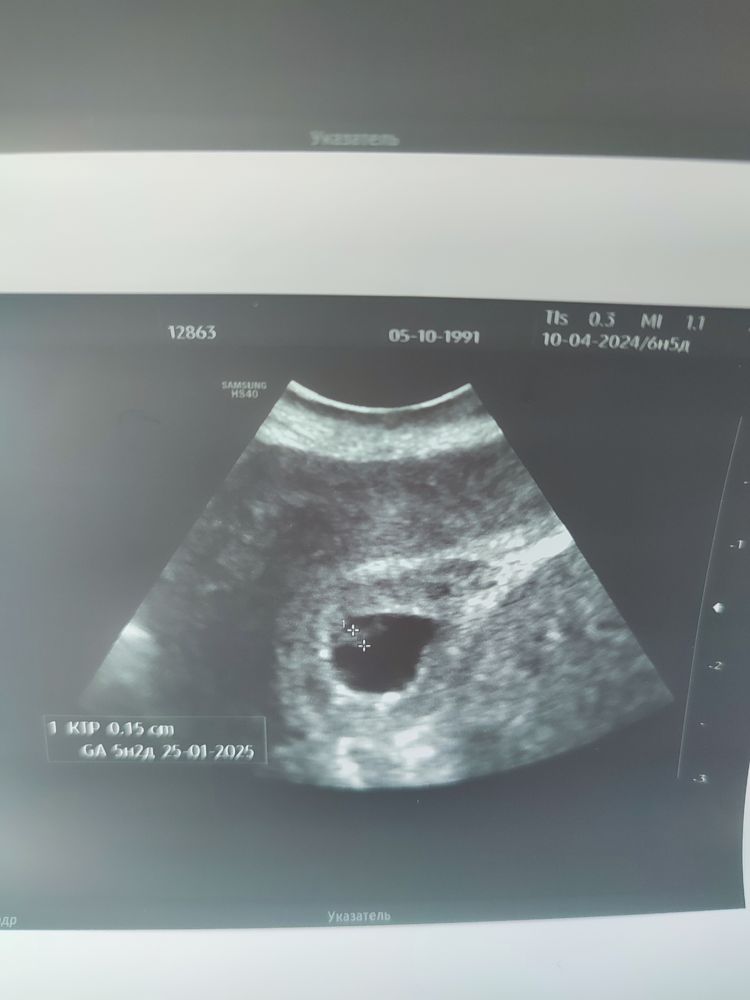

ta987nya, врач УЗИ очень осторожен, но в целом "только ждать. Понятно, к какому исходу стремимся, но чудеса бывают". Ктр 1,5мм Свд 10 мм Меня очень смущает ктр: как будто измерен поперек, а не вдоль. Выложу фотку в пост. Но понимаю, что цепляюсь за призрачное и врачу виднее.

Екатерина, если реально ктр вырос с 1,1 до 1,5 то хорошего мало....но на фото как-будто больше эмбрион....а пя 10 мм - норма для такого срока. Не представляю, где вы силы берете ждать и надеяться. Это ж уже двинуться можно.

Екатерина, кстати да, ктр как будто поперек отмечен на снимке. Странновато